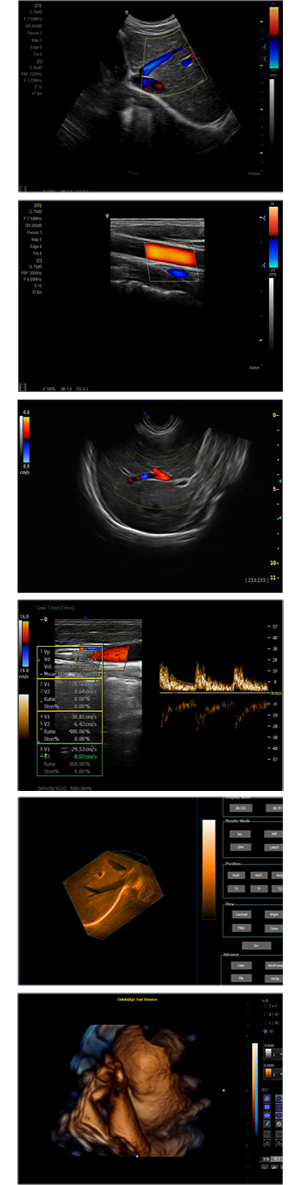

XF-7800型,秉承先鋒彩超技術(shù)之精華,擁有高雅大氣的獨(dú)特外型,為最新一代應(yīng)用型數(shù)字彩色多普勒診斷系統(tǒng),魅力與實(shí)力相融合。可廣泛適用于腹部、婦產(chǎn)科、心臟、小器官、乳腺、肌骨及外周血管等諸多方面的診查,讓您在臨床超聲診斷應(yīng)用領(lǐng)域得心應(yīng)手,綻放異彩!

突破的成像技術(shù)

● 3D/ 4D成像技術(shù)/限7800選配

● 應(yīng)用于腹部、腎臟、泌尿系統(tǒng)、產(chǎn)科、婦科、盆腔、大動脈、肌肉組織、小器官、乳腺、心臟等

● 能量多普勒成像(PDI)

● 彩色血流量圖(CDE)

● 脈沖頻譜多普勒成像(PW)